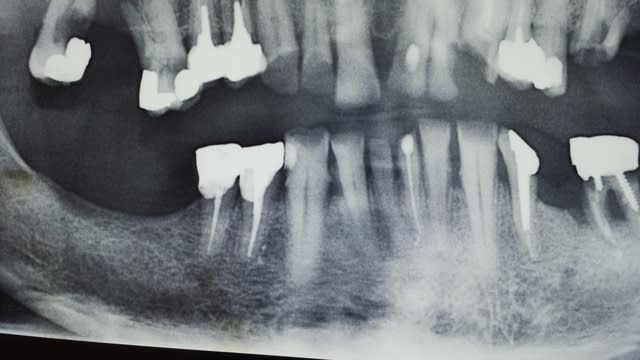

Bonjour,le patient s'est présenté au cabinet pour une réhabilitation prothétique, sa principale préoccupation étant le secteur incisif mandibulaire très usé par le bruxisme. Ci joit son ancienne pano (des soins ont été déjà effectués depuis par son ancien dentiste extraction 36 ccm 34).Le secteur incisif mandibulaire étant très délabré j envisagais une réhabilitation prothètique fixe de 33 à 43 avec élévation de la DV. Les incisives réstantes ne sont pas mobiles mais très abimées. Qui serait pour des ccm solidarisées sans 33 43 sans extractions? Ou pensez vous qu un bridge 33 43 après extraction 31 ,41 serait plus judicieux? Merci beaucoup pour vos avis.